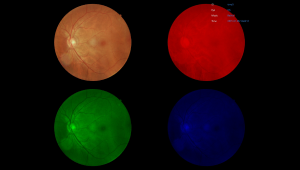

Вбудовані фільтри

NFC-700 надає фільтри без червоного, негативу плівки, RGB, градації сірого, щоб користувачі могли змінювати або застосовувати фотоефекти до зображення для різних цілей.

Порівняння зображень

Користувачі можуть обирати різні періоди або ракурси знімків для порівняння.